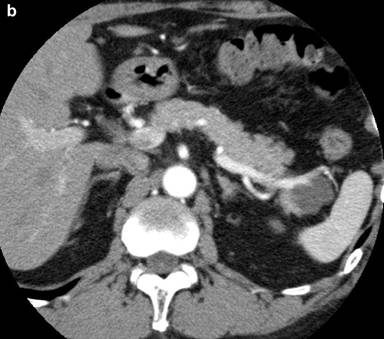

A 53-year-old man was incidentally found to have a cystic tumor in the tail of the pancreas after undergoing an abdominal ultrasound (US), which showed a 41x33 mm cystic mass in the pancreatic tail. He had no abdominal symptoms. The tumor markers, including DUPAN 2, and carbohydrate antigen 19-9, were within the normal ranges. The patient was referred to our hospital for further investigations. A contrast-enhanced CT scan (Figure 1) showed a non-enhanced cyst between the spleen and the pancreas with no solid component. Magnetic resonance cholangiopancreatography (Figure 2) revealed that the main pancreatic duct was regular and had no dilatation, and there was no communication between the cyst and the pancreatic duct. Magnetic resonance imaging (MRI) showed a lesion with a slightly high signal on a T1-weighted image; the lesion, which was well circumscribed, was in the tail of the pancreas (Figure 3). MRI on a T2-weighted image also showed the lesion with a high signal. The cystic tumor was negatively visualized on the PET image. Endoscopic ultrasound (EUS) was performed, which showed a 55x31 mm pancreatic tail lesion with a solid and cystic mixed component (Figure 4a). An endoscopic ultrasound-guided fine-needle aspiration biopsy in a trans-gastric approach of this lesion suggested a diagnosis of a benign squamous cyst (Figure 4b).

Figure 2. Magnetic resonance cholangiopancreatography revealed that the main pancreatic duct was normal and had no dilatation. |